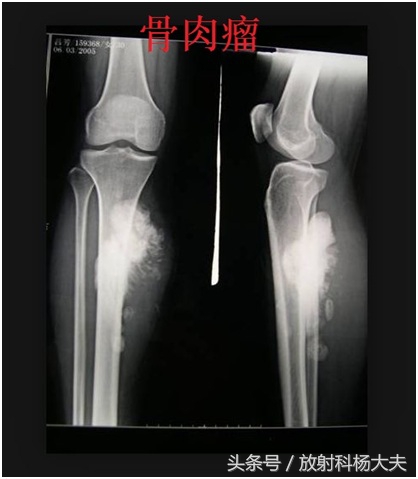

在骨关节的X线片上,通常在骨骼或骨骼边上看到这种高密度的类似骨骼一样东西,我们会考虑哪些?骨肉瘤,软骨肉瘤,创伤性骨炎,还有某些疾病引起的钙化,骨化等等。

比如,下面的图,都是恶性的。